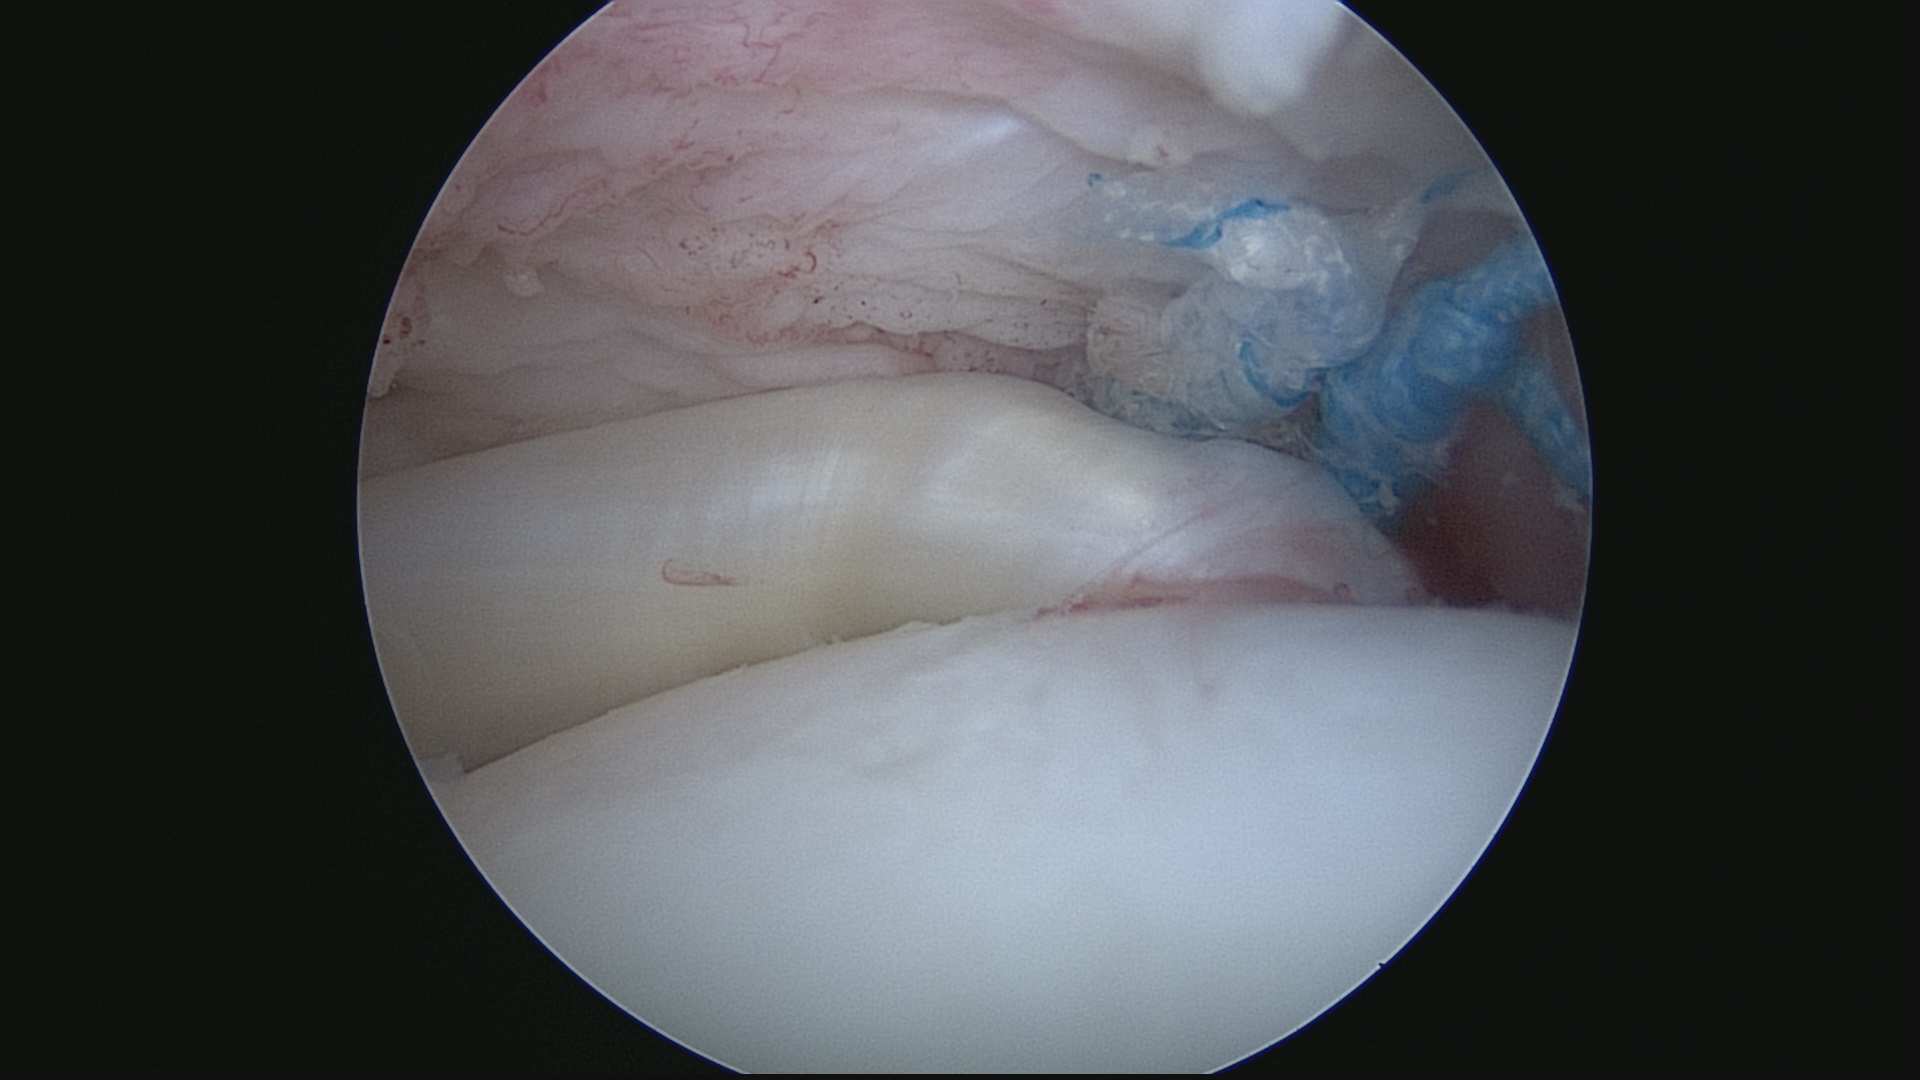

Rupture supraspinatus (Vue sous acromiale)

Mise en place des ancres (Vue sous acromiale)

Mise en place des ancres (Vue endoarticulaire)